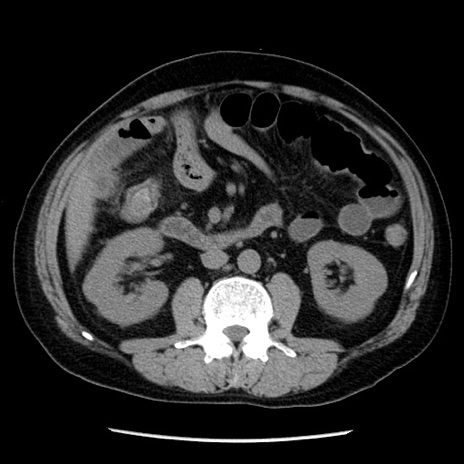

症例29(横断像)

【症例】40歳代男性

【現病歴】2日前から胃痛あり。徐々に周期的な激痛に変化した。本日になっても激痛があるため受診。

【身体所見】意識清明、BT 38-39℃台あり、腹部:膨満、やや硬、右下腹部に圧痛あり。

【データ】WBC 8500、CRP 23.26